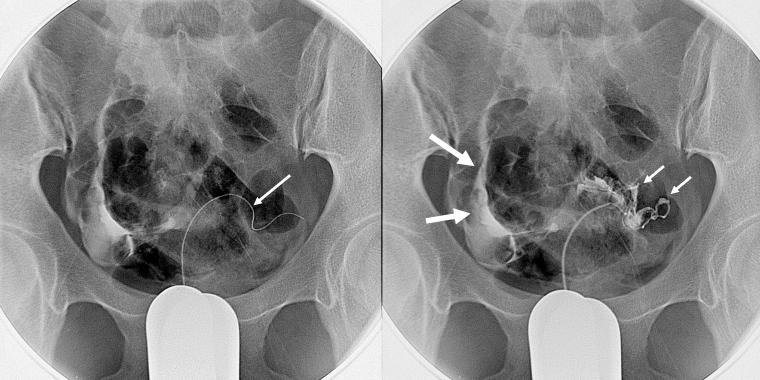

精索静脉栓塞术是怎样进行的呢?简单的说,就是穿刺股静脉,将选择性导管在电视透视监视下,经股静脉、髂静脉、下腔静脉、左肾静脉一直插到左侧精索静脉,造影明确曲张静脉的程度以及有无解剖变异等情况后,选择适宜的栓塞剂将其栓塞,血液就不会经其倒流而产生阴囊部位的静脉曲张了,患者也不会因为整天在两腿之间挂着个“大袋子”而行动不便了。由于解剖结构上的不同,右侧精索静脉一般不发生曲张,故通常不需要栓塞治疗。

精索静脉栓塞术中造影所见